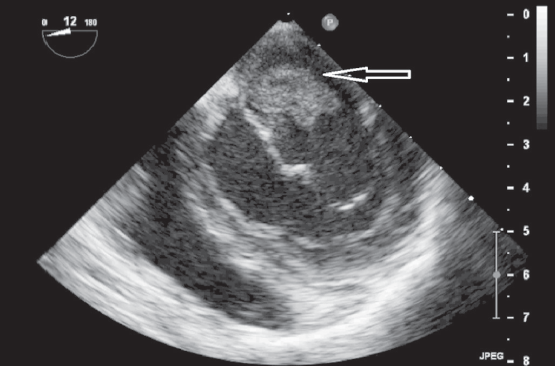

The optimal time for surgery on the heart valves in patients with active infectious endocarditis (IE) is still controversial. It is a well known fact that cerebral, coronary or renal thromboembolism is the most common cause of death in patients with left-sided IE. Thromboembolism can develop before the appearance of clinical manifestations of the destruction of the valvular apparatus of the heart. Currently, early surgical intervention is considered as the most effective method of treatment of many forms of active left-sided IE. Early surgery involves performing surgical correction until the completion of a full antibiotics course. We present the clinical case of early surgical correction of the patient (A., 16 years) with mitral valve infectious endocarditis. The disease was acute, with recurrent embolisms to the right kidney with infarction and to the left clavicle with osteomyelitis. Surgical intervention was performed as a matter of urgency; surgical access – right-sided anterolateral thoracotomy. The girl was operated on the 4th day of the hospitalization to our hospital. However, time of treatment was lost at the prehospital stage and rapid mitral valve destruction did not allow to repair the valve. Therefore, the mitral valve replacement was performed. The postoperative period was favorable. On the 3rd day after the operation, the girl was transferred to the cardiology department. On control ECHO after 3 years: myocardial contractile function is good, EF 65%, the function of the MV prosthesis is not impaired.